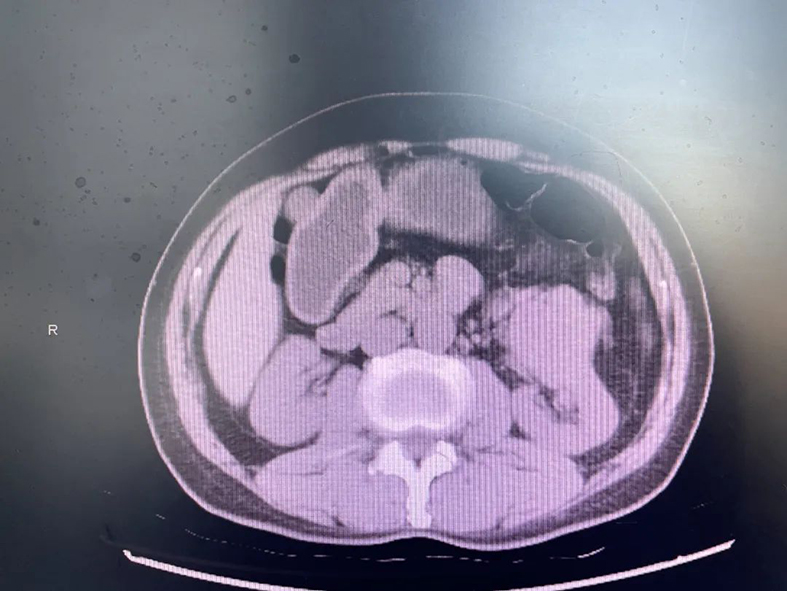

患者为男性,69岁,因体检发现左肾肿物入院,后经泌尿系CT检查提示:左肾肿瘤,大小约5.4*4.7cm,位于左肾下极内侧及肾唇,与左肾动静脉、左侧输尿管关系密切。

由于患者肾功能存在异常,血肌酐118.7umol/L,若依照传统的手术方式行左肾根治性切除术,患者术后肾功能不全必然加重,需要血液透析治疗的可能性极高;若行肾部分切除术,那将会保存很多肾单位,极大地提高患者术后生活质量。但是,肿瘤位置特殊,能否完整、充分、安全地切除肿瘤,将是一个巨大挑战。